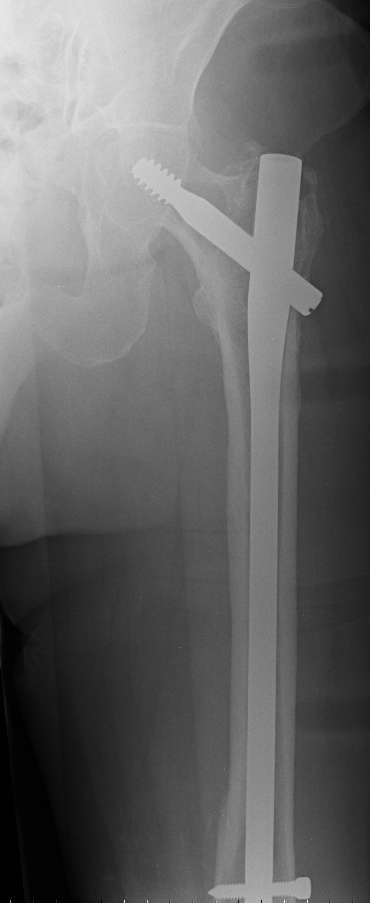

4. We could treat this fracture like there is no a nail - new locking plates allow for secure fixation.... two similar cases are attached...

Images sent by Professor Kanlic look nice, very good job. Excellent achorage in distal fragment. However, unicortical screwing or bicortical

makes a difference, also for locked screws. Proximal fragment unicortical fixation may present stability not easlily predictable. Certainly its stability for wheelchair should be sufficient. Full weight bearing can not be mentioned for this case. If minimal bearing is allowed full weight

Gamma nail exchange may probably fit the criteria of optimal and minimal invasivness, indeed. Removal could be relatively fast due to large intramedullary diameter seen on X-ray.

Images sent by Professor Kanlic look nice, very good job. Excellent achorage in distal fragment. However, unicortical screwing or bicortical makes a difference, also for locked screws. Proximal fragment unicortical fixation may present stability not easlily predictable. Certainly its

stability for wheelchair should be sufficient. Full weight bearing can not be mentioned for this case. If minimal bearing is allowed full weight

Gamma nail exchange may probably fit the criteria of optimal and minimal invasivness, indeed. Removal could be relatively fast due to large

intramedullary diameter seen on X-ray.